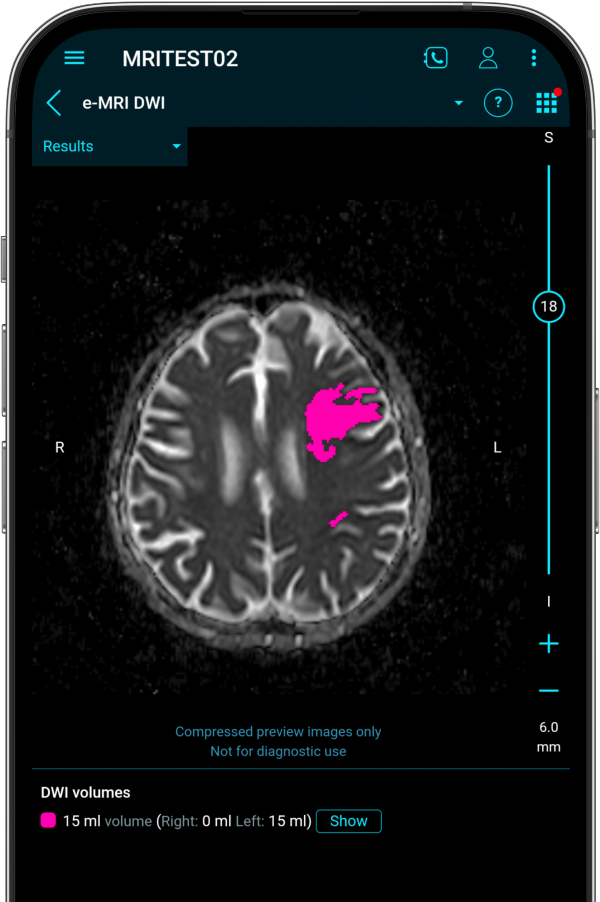

MRI

Supporting Advanced

Imaging Assessments​

e-MRI is a visualization and processing tool which provides both analysis and viewing capabilities for Diffusion Weighted Imaging (DWI) and Dynamic Susceptibility Contrast (DSC) perfusion, allowing for side-by-side viewing of different MR sequences along with the results.